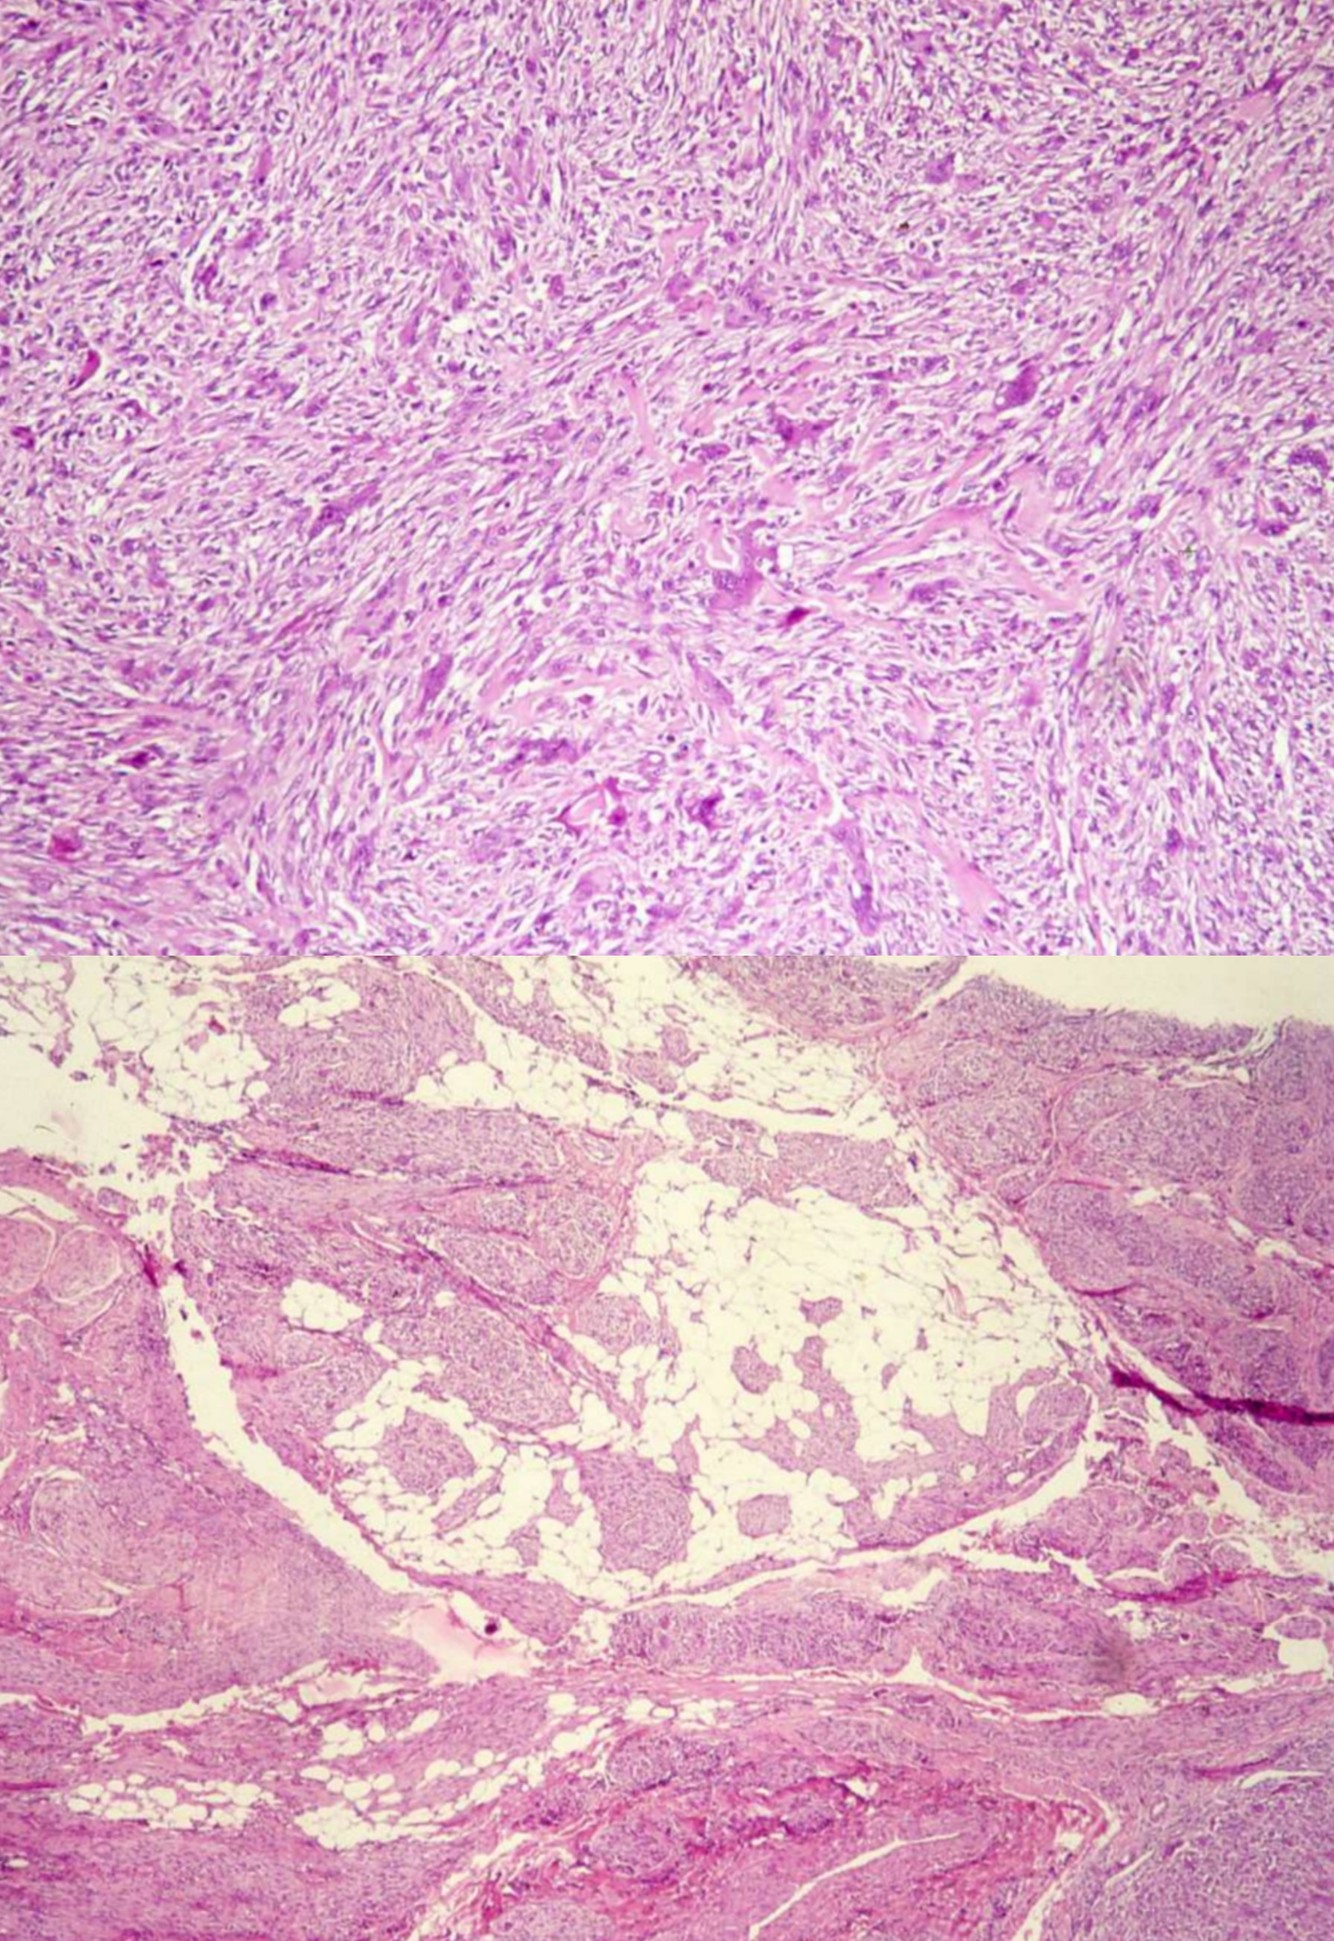

Myxofibrosarcoma

• Highly complex karyotypes, often 6p-, 9q+, 12q+

• A myxoid subtype of undifferentiated pleomorphic sarcoma

• elderly patients, predominately in extremities, 2/3 within dermis and subcutis, remainder in deep skeletal muscle or other deep tissues

• Retroperitoneal masses with similar histologic features are most likely dedifferentiated liposarcoma

• Gross:

• Superficial tumors are multiple myxoid nodules, deep tumors are a single mass with infiltrative margins

• High grade tumors often have tumor necrosis

• Histology:

• Multinodular tumor composed of pleomorphic spindle cells in myxoid background

• “Pseudolipoblasts” may be seen (tumor cells with cytoplasmic vacuoles filled with mucin/myxoid material)

• More solid areas are often seen similar to typical undifferentiated pleomorphic sarcoma

• Curvilinear vessels (thick walled with broad arc) with condensation of cells around vessels is characteristic, incomplete fibrous septa, myxoid stroma (at least 10% of tumor) and infiltrating immature dendritic cells (Am J Clin Pathol 2003;119:540)

• Has infiltrative periphery and often sends out long tentacles with frequent positive margins

• High grade tumors are more cellular with atypical mitotic figures, hemorrhage, necrosis and possibly bizarre multinucleated giant cells

• Rarely epithelioid

• Stains:

• No specific stains exists; +/- vimentin, acid mucins, CD34

• Negative: Fat stains, S100

SYNOVIAL SARCOMA

• Genetics:

• t(X;18)(p11.2; q11): SYT-SSX1 genes in 90%; can detect via PCR

• t(X;18)(p11.21;q11): SYT-SSX2 fusion genes; variants can be detected by optimizing RT-PC

• p16INK4A gene deletion in 74%

• High expression of EZH2 helps to distinguish poorly differentiated synovial sarcoma from monophasic and biphasic subtypes

• Clinical:

• deep seated mass present for years around large joints (80% in knee and ankle) in young adults (age 20-40), M > F

• 10-15% metastasize to lung and pleura, bone, regional nodes

• Minute (< 1 cm) tumors of hands and feet, F > M, median 29 yo

• Well circumscribed, firm, gray-pink

• Focal calcifications on Xray

• Biphasic, monophasic or undifferentiated

• Biphasic have spindle cells resembling synoviocytes and plump epithelial cells forming glands/cords

• Monophasic lack the epithelial cells

• Spindle cells are arranged in plump fascicles with hyalinization and distinct lobulation accompanied by mast cells, occasional osseous or cartilaginous metaplasia, focal whorling

• +/- hemangiopericytomatous vascular pattern

• Monophasic much more common than biphasic.

• Stains

• Positive: Keratin, EMA, S100, bcl2, TLE1, CD99, vimentin, CEA, CD57, E-cadherin (50%), S100 (30-40%), c-kit , nuclear beta-catenin

• Negative: CD34, desmin, myogenin, h-caldesmon, CD141, WT1, FLI-1

• Mucin - spindle cell areas, PAS positive - epithelium, reticulin highlights biphasic pattern

• Poor prognostic factors: high histologic grade (based on MIB1 index and necrosis), SYT-SSX1 vs. SYT-SSX2 gene fusion